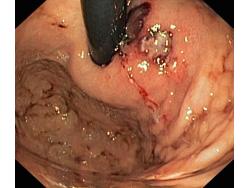

Krwawienie